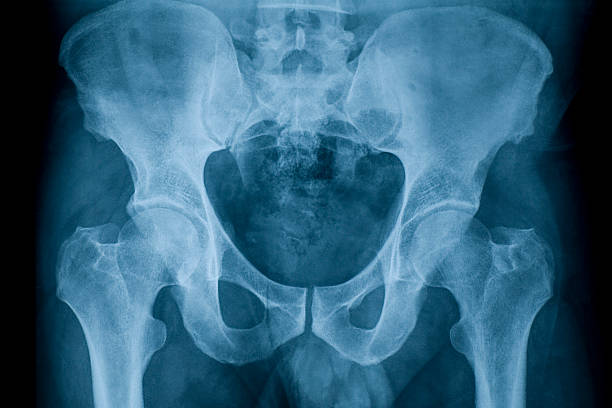

Alexandra Kis din Bucureşti avea o tumoră la gât cât oul de găină. După doar 3 luni de tratament, tumora a dispărut pentru totdeauna. La fel de miraculos s-a vindecat Sandu Marin din Craiova. Având o formă agresivă de cancer osos, dr. Udrişte l-a avertizat că tratamentul este necesar să dureze cel puţin doi ani. După doar câteva luni, s-a prezentat la spital, unde chirurgul ortoped îl programase pentru operaţie la şold. Nu a mai fost cazul. Privind rezultatul analizelor, chirurgul a rămas uluit, zicând: „Ce ai făcut Sandule? Nu mai este nevoie de operaţie. Osul e complet refăcut”.